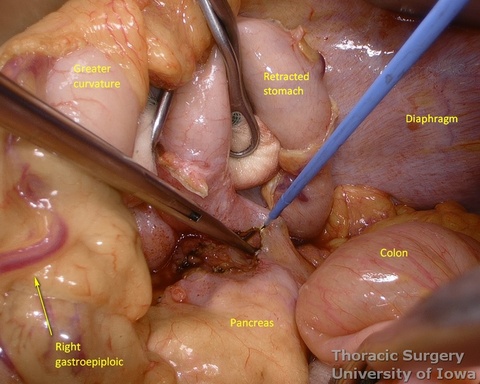

- Procced with mobilization of the stomach. The course of the right gastroepiploic artery is determined.

- The gastrocolic ligament is incised in its avascular portion between the terminal branches of the right and left gastroepiploic vessels, and the lesser sac is entered.

- The gastrosplenic ligament is divided towards the hiatus, taking care to stay away from the gastroepiploic arcade.

- Divide short gastric vessels with an energy device with care to avoid traction injury of the spleen.

- Fundus of the stomach is dissected free all the way to the esophageal hiatus dividing gastro-phenic ligament and remaining adhesions.

- The greater curvature of the stomach is then mobilized towards the pylorus, dividing the gastrocolic ligament no closer to than 1.5–2 cm to the right gastroepiploic vessels, while protecting the vessels with the fingers of the retracting hand. In morbidly obese patients the right gastroepiploic artery may not be visible or palpable. A Doppler probe is used then to identify its course and origin from the gastroduodenal artery.

- Posterior adhesions of the stomach are taken down.

- Peritoneum is incised, protecting the splenic artery and pancreas. 1-2 mm posterior gastric artery, originating from the proximal splenic artery fs present (in half of individuals) and is divided.

- Once the stomach is mobilized and reflected anteriorly, the left gastric vascular pedicle is identified and dissected close to the origin for adequate lymphadenectomy. Care is taken to not injure splenic artery and pancreas.